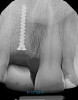

A 56-year-old female patient was referred for the evaluation of tooth No. 8 (Figure 4 and Figure 5). A periapical radiograph indicated that the tooth had undergone apicoectomy and received an excessively long post (Figure 6), and a cone-beam computed tomography (CBCT) scan of the site revealed a lack of buccal plate bone (Figure 7).

(6.) Pretreatment periapical radiograph.

Figure 6

(21.) Postoperative periapical radiograph taken immediately after placement of the implant at site No. 8 demonstrating implant positioning centered with the planned location of the gingival zenith and two titanium alloy tacks that were used to stabilize the resorbable membrane apically.

Figure 21